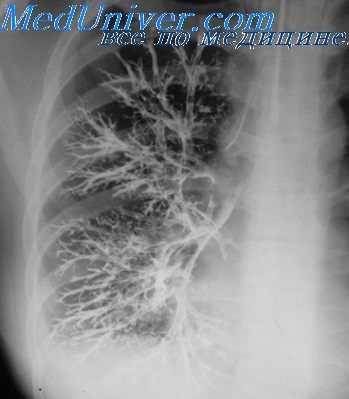

Одномоментная двусторонняя бронхография. Бронхография при обильном количестве мокроты

Б. К. Шаров (1962, 1965) разработал методику «аспирационной бронхографии». Она заключается в том, что при выполнении общей бронхографии конец катетера проводится в главный бронх и контрастное вещество (сульфоиодол) вводится в момент задержанного глубокого выдоха. После окончания введения больной делает глубокий вдох и контрастное вещество аспирируется в бронхиальное дерево.

Если количество контрастного вещества уменьшить до 7 — 12 мл, достигается получение контурных бронхограмм, позволяющих оценить состояние рельефа бронхиального дерева. Б. К. Шаров считает, что распределение контрастного вещества при аспирационной бронхографии отражает изменение легочной вентиляции, что позволяет рассматривать этот метод как функциональную бронхографию.